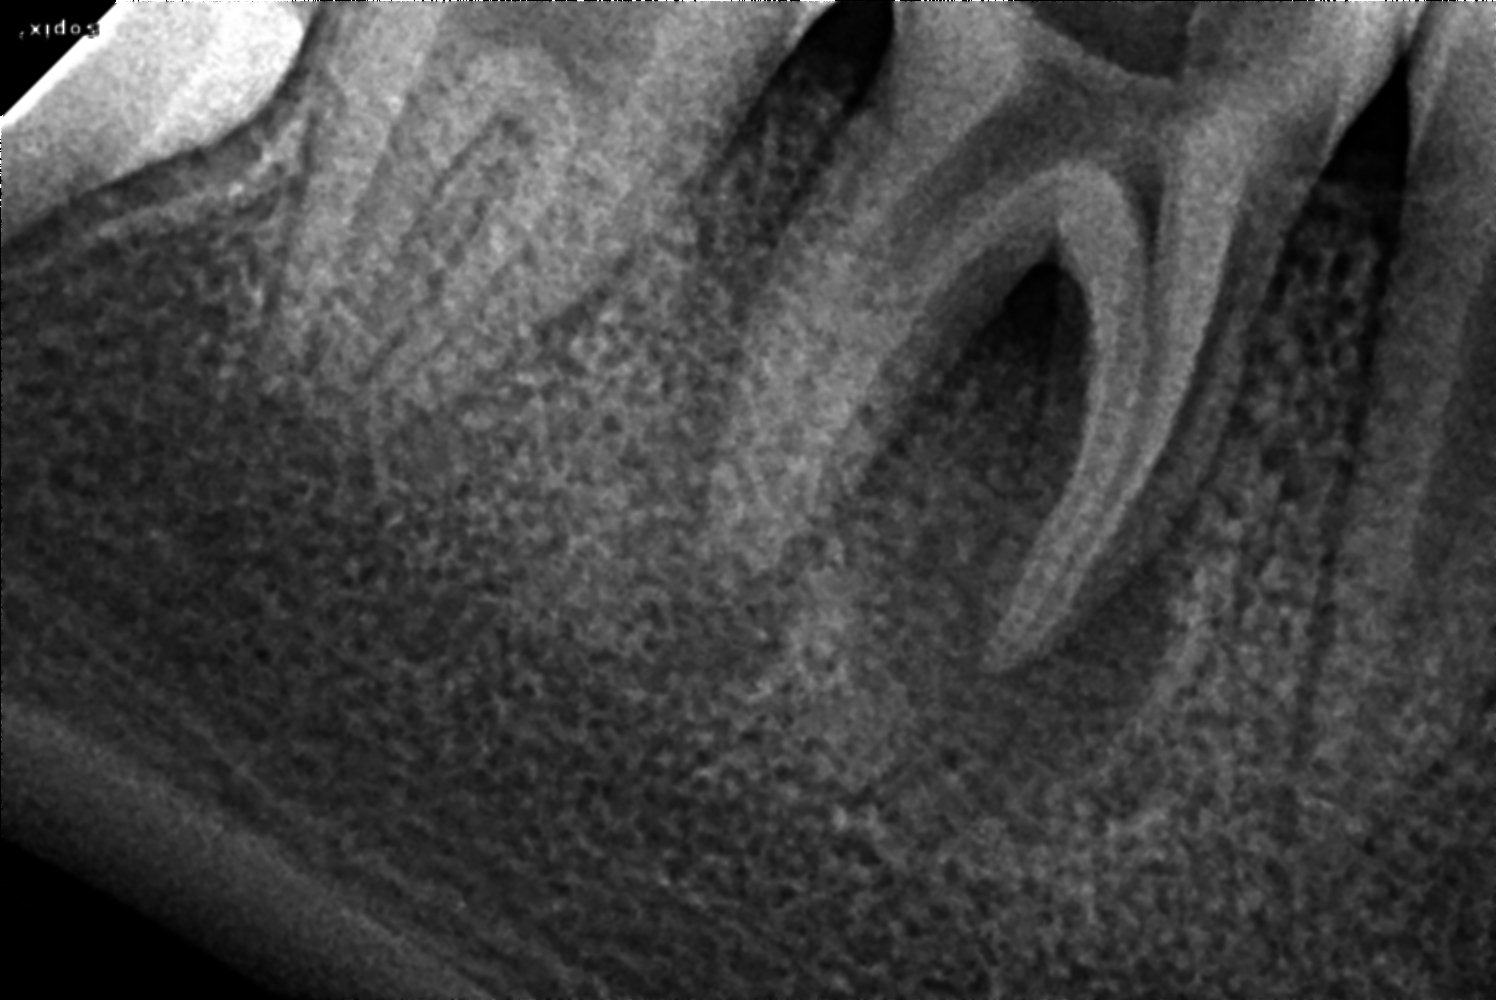

Treatmentsobturation done

bioceramic sealer

composite filling

77

Date of visit18/11/2021

C/C & Rx plansnon vital

Treatmentsacess opened 46

MB 17.5 ML 17 (4 % 25)

DB 17 DL 18.5 (6 % 25)